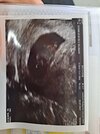

To ja się dzisiaj pochwalę zdjęciem z usg

Mdłości mi praktycznie odeszły, więc się zamartwiałam. Wg poprzedniego usg powinno być 7+2, a tutaj niespodzianka, 8+2 i serduszko bije

byłam u innego lekarza, z lepszym sprzętem. Mój prowadzący jest stary i ślepy i chyba jednak sprzęt ma słaby

teraz w końcu terminy mi się zgadzają, a nie ciąża młodsza z każdym usg